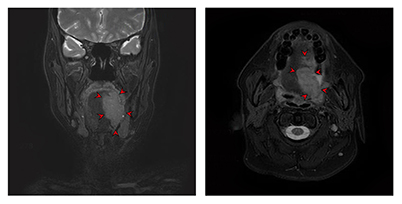

![[좌측 설암 전산화단층촬영 이미지]](../res/images/cancer/21_2_3.jpg)

[좌측 설암 전산화단층촬영 이미지]

전산화단층촬영(CT)과 더불어 임상적 병기 결정을 위한 정보를 얻는데 사용합니다. 연조직에 발생한 암종의 경우 자기공명영상이 더 선호되고 있어 설암 환자의 경우 자기공명영상이 필수적이라 할 수 있습니다. 촬영 전 구강 내 보철물은 제거하고 촬영하는 것이 상의 왜곡을 막기 위해 필요합니다.

[ 좌측 설암의 자기공명영상 촬영 이미지 ]